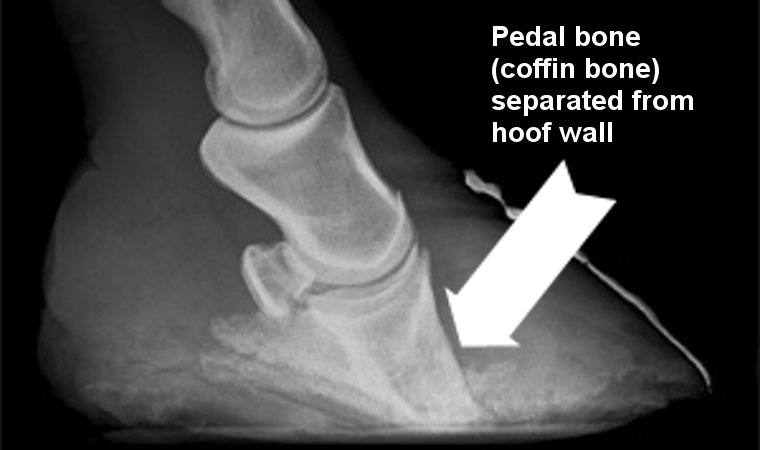

In the foot of the normal horse or pony, the hoof wall and the pedal bone (the lowest bone in the foot) are joined together by velcro-like structures called the laminae. When a horse or pony has laminitis these laminae become inflamed and pull apart - this is extremely painful, and results in the pedal bone dropping away from the hoof wall. This can be seen in the x-ray above.

If an episode of laminitis goes on for some time, or if there are repeated occurrences, the damage can become irreversible leading to rotation of the pedal bone and permanent foot pain, and in extremely severe cases euthanasia.